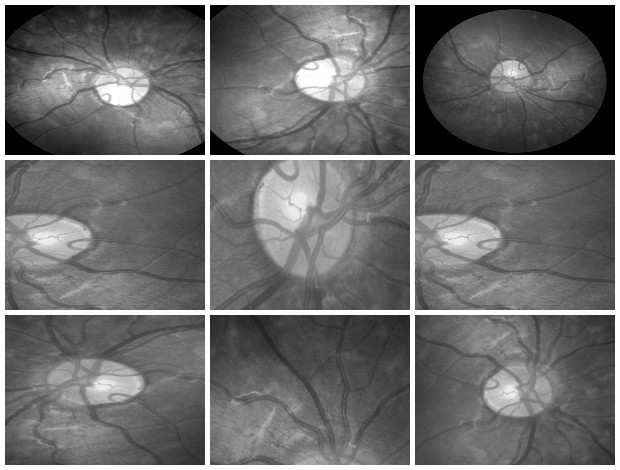

Hello world! In December of 1895, Wilhelm Röntgen the bones of his wife’s hand in the first X-ray photograph. “I have seen my death,” she said. This breakthrough had an incredible influence on 20th-century medical treatment. And latest Deep Learning advances open up new possibilities in this field. revealed Deep Learning has found great success in computer vision and other areas. And now it is actively transforming the world of medicine. AI helps doctors make more accurate diagnoses faster. Today we would like to share our thoughts and investigations into very promising direction: Human in the loop AI for medical image analysis within a single environment — . Supervisely Our platform allows to manage and annotate data, train NNs, apply them for automatic pre-annotation and then deploy them as API. Challenges with medical images IBM researchers that medical images, as the largest and fastest-growing data source in the healthcare industry, account for at least 90 percent of all medical data. estimate Challenge 1: data privacy Medical data is still personal and not easy to access. And due to data privacy concerns most of the public health centers are reluctant to share the data. Challenge 2: size of annotated data Annotation process is hard to outsource and only expert physicians can analyze medical images. This limitation leads to high costs and to the lack of annotated data. Challenge 3: quality of annotation tools Annotation tools, that can be used to extract insights from medical images, are still limited, in most cases publicly unavailable and requiring most analysis to be done manually. Challenge 4 (consequence of 1 and 2): segmentation challenge Datasets for segmentation task are typically extremely small compared to large public datasets of common images (COCO, PascalVoc and so on). Due to the size of datasets it is difficult to train very deep neural network architectures. Objects of interest can vary in size, shape and position. In combination with the “soft” boundaries it produces additional problems. Our goals We are going to overcome Challenge 3 and Challenge 4: give the industry end-to-end solution that makes human experts more efficient and automates routine tasks with powerful AI technologies. Supervisely: user interfaces We realize, that there is still a lot of work ahead: increase the number of convenient annotation tools and add the support of DICOM format, three dimensional images, sequences of images and so on. But these are only technical issues, first steps are already done and promising results are obtained. We are passioned to accelerate medicine and happy to be a part of global research community that drives deep learning revolution to healthcare. There could be no more important application of this new capability [deep learning] than improving patient care — Jensen Huang, NVIDIA CEO and co-founder Case-study: blood vessel segmentation in retina images There are a lot of Deep Learning medical applications in imaging: tumor detection, tracking tumor development, blood flow quantification and visualization, dental radiology and much more. Because we are not doctors, we looked for data we understand more or less. That’s why we decided to make research on blood vessel segmentation. Let’s take a look to one of the most popular public datasets in this field: (STructured Analysis of the Retina). STARE Dataset contains 28 annotated images with resolution 999 × 960. We consider the case that we have only . Other images will be used for final evaluation of quality. All training images are below: 6 annotated images in training dataset Here is the whole training dataset we use. This scenario is pretty close to real world: medical doctor annotates few images, then neural network is trained on this data and applied to other images for pre-segmentation. Then doctor just corrects the NN predictions. Such approach is called Human in the loop AI. It is aimed to significantly accelerate efficiency of human expert. PS. Thanks to Supervisely entire research took 2 hours without haste ☕. Step1: training data augmentation We had only 6 annotated images. To train NN we have to automatically increase the size of dataset. Supervisely has special module to perform augmentations: DTL (Data Transformation Language). It allows to configure entire augmentation process in a simple json-based format and perform it in a few clicks. How DTL query interface looks like In this use case we did horizontal/vertical flips and relatively big random crops. We got 264 training examples from only 6 annotated images. Here is the visualization of computational graph that we applied to our data: Resulted crops after augmentation Step2: train neural network There are few state of the art Neural Networks for semantic segmentation in Supervisely. One of them — our custom UNet-like architecture. It was chosen because: we have small training dataset, it is accurate and fast to train. Also we use combination of Binary Cross Entropy and Dice losses because of class imbalance problem. Vessels pixels covers only few percents of image area in contrast to background pixels. We trained NN 50 epochs. It is interesting to visualize Neural Network predictions during training. We take unseen image and apply NN after each epoch. Here you can see how our NN becomes smarter over time. Supervisely supports multi GPU training. Each epoch takes around 20 seconds on four GPU. Total training time — around 17 minutes. Step3: automatic pre-segmentation We applied NN to new images. Let’s compare predictions with ground truth. : NN predictions, : ground truth Left Right As you can see from this comparison every relatively bold vessels are segmented. There is no noise. It means that the human only have to draw few hairlines with “polyline” tool. Also, as we understand real data has much bigger resolution that public data we use in this experiment. We think that this fact is crucial for the quality of hairlines segmentation. Resolution of publicly available images is not enough. Look at this example: do you see the vessels that are annotated by doctors? Left: meme, Middle: original image, Right: doctor’s annotation Step4: manual correction As you can see from images above the quality of automatic pre-annotation is pretty good. It is much more easier and faster to correct NN predictions than annotate from scratch manually. We were not lazy and made time measurements: how much time we need for manual annotation from scratch vs correction of NN predictions. Manual annotation from scratch: . Correction of NN predictions: . 36 minutes / image 4 minutes / image Conclusion is obvious. Final thoughts Deep Learning has a huge potential in medical image analysis. AI is changing the way doctors diagnose illnesses. Main important difference between doctor and deep learning algorithm is that doctor has to sleep. Neural Network can process millions of images and can be continuously improved. Human in the loop approach and automatic segmentation with Supervisely will let us create large datasets faster. All steps are done without coding. It means that user with no ML background have access to state of the art AI. So ML community will build more services to help doctors provide better and quicker treatment. Let’s make the future together. If you found this article interesting, then let’s help others too. More people will see it if you give it some 👏.